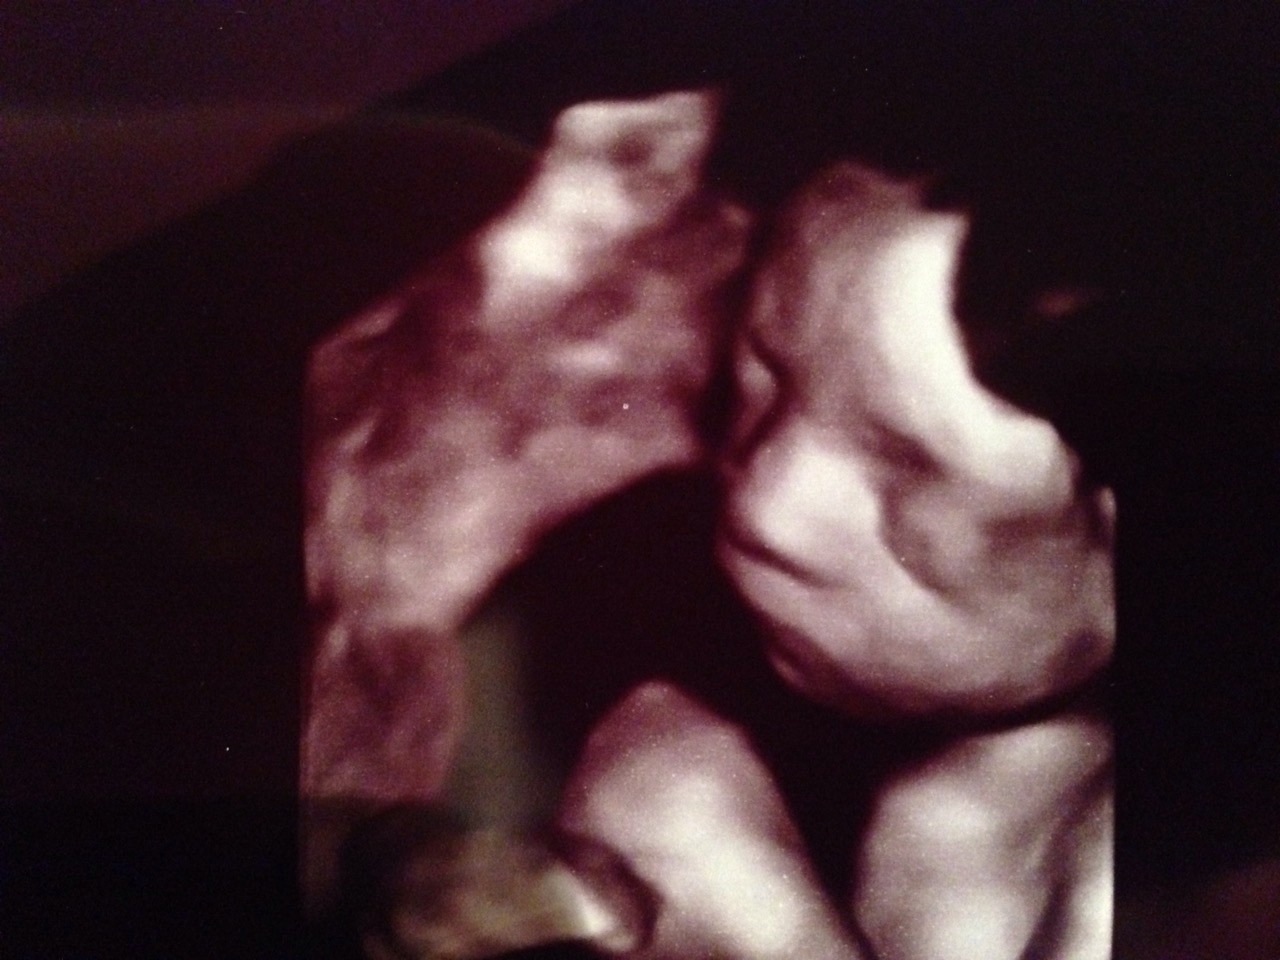

Toll dass der US schön war! Eine echt süße Maus hast Du da im Bauch! Tolles Bild! Und sie ist noch sooo zierlich! Voll süß!